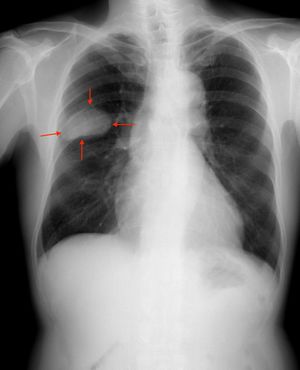

الرئة اليمنى، الجانب S2-S3 من سرطان الخلايا الصغيرة.